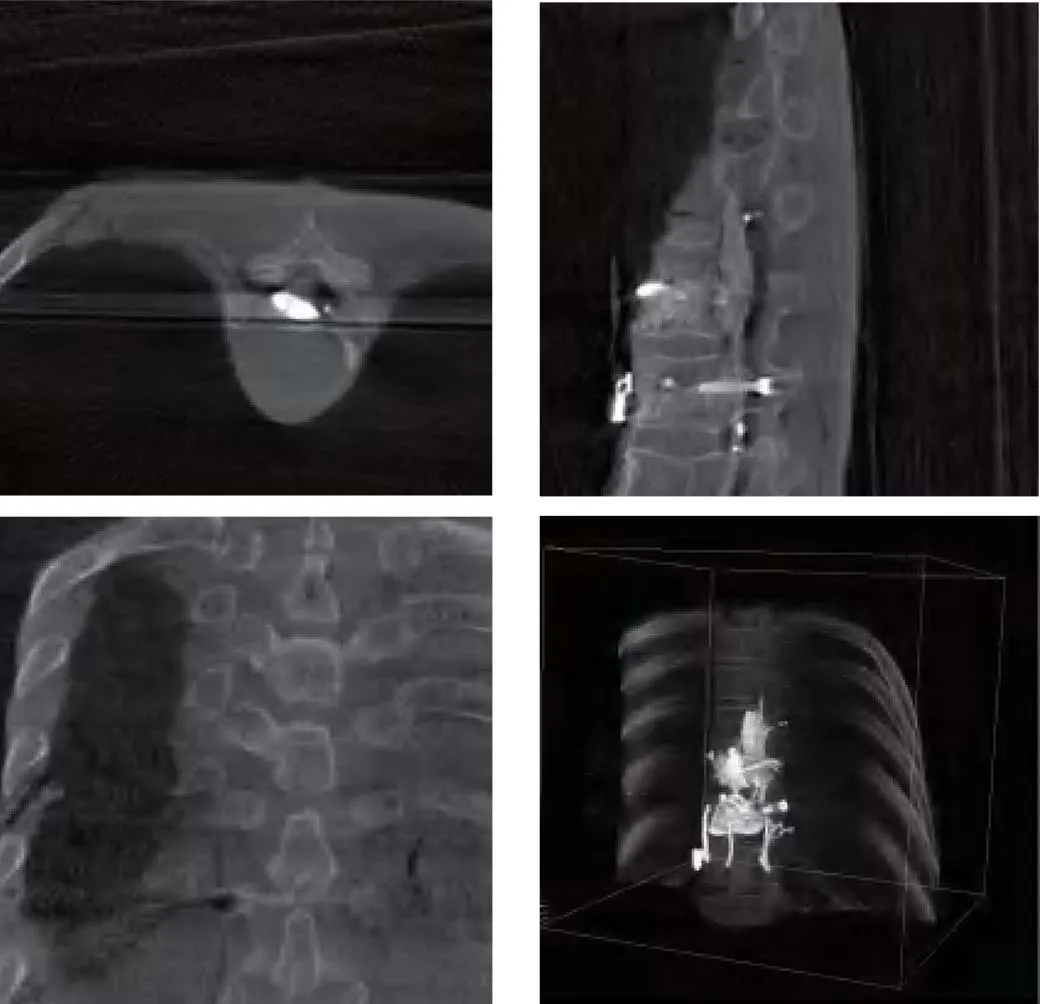

Metal artifact removal technology to remove artifacts caused by metals such as metal nails or metal stents. |